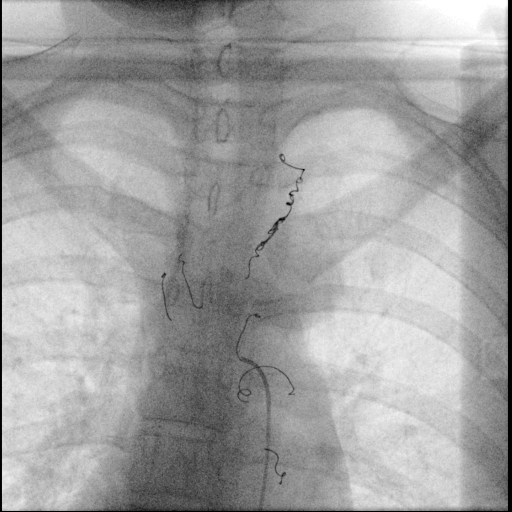

第一步是动脉造影。医生经股动脉穿刺,将一根纤细的导管送至胸主动脉,注入造影剂。瞬间,清晰的血管影像实时呈现在数字减影血管造影(DSA)屏幕上。可以明显看到,肿瘤区域有数根异常增粗、迂曲的血管(主要为肋间动脉)正如同“河流”般源源不断地向肿瘤组织输送血液。

接下来是手术最精妙的环节:超选择性血管栓塞术。满新贺操控着更细微的微导管,如同驾驶飞船在复杂的血管迷宫中穿梭。他们凭借精湛的技艺和丰富的经验,小心翼翼地避开供应正常脊髓和重要器官的血管分支,将微导管头端精准地置于每一根为肿瘤供血的靶血管内。

“位置完美,可以栓塞!”确认无误后,一种特制的栓塞微粒被缓缓注入,这些微粒随着血流精准地沉积在肿瘤的血管巢中,形成栓塞,彻底阻断了血流。屏幕上,原本显示肿瘤血供的浓密“染色”区域逐渐变淡、消失。

手术历时一个多小时,全程患者清醒,仅在大腿根部留下一个微小穿刺点。术后造影证实,肿瘤的主要供血动脉已被成功“封闭”。